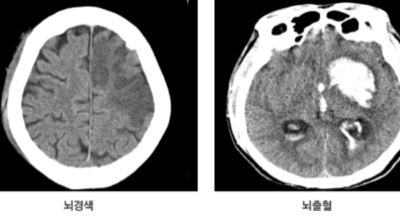

뇌출혈이란?

뇌출혈 전조증상을 살펴보기에 앞서 뇌출혈이란 구체적으로 무엇인지 알아보겠습니다.우리 신체의 구조상 뇌는 산소를 저장할 수 없게 되어 있어요. 그렇다면 어떻게 필요한 산소를 공급받을 수 있을까요? 우리 뇌는 산소와 영양분을 공급받기 위해 우리 몸의 구석구석을 누비는 혈관에 의존해 도움을 받습니다.

만약 이런 혈관이 파열되고, 공급되던 산소가 누출되어 뇌 조직에 도달하지 못하면 어떻게 될까요? 혈액이 고이며 뇌에 부담(압력)을 주며, 응급조치가 없이 3~4분 이상 산소가 결핍된 상태가 지속되면 뇌세포는 죽습니다. 그러면 함께 영향을 받는 신경 세포가 제어능력을 잃게 되고, 우리 몸의 기능도 함께 손상되는 것으로 보입니다.